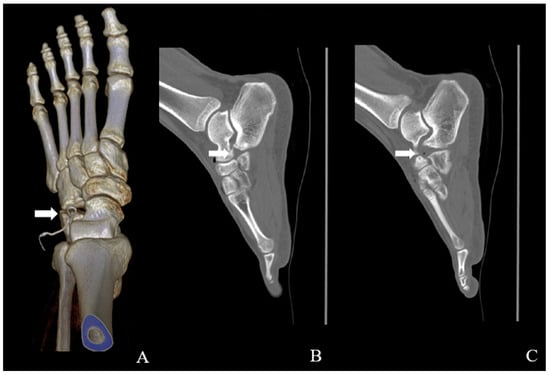

Multiple Calcaneus Secundarius Ossicles Presenting with Anterior Foot Pain: A Case Report Highlighting Characteristic Imaging Features

by Ki Jin Jung, Eui Dong Yeo, Jeong Han Nam and Woo Jong Kim

Background: Calcaneus secundarius (CS) is an accessory ossicle located at the anterior aspect of the calcaneus and is typically an incidental and asymptomatic radiographic finding. However, it may become symptomatic following trauma or repetitive mechanical stress and can mimic anterior calcaneal process [...] Read more.

Background: Calcaneus secundarius (CS) is an accessory ossicle located at the anterior aspect of the calcaneus and is typically an incidental and asymptomatic radiographic finding. However, it may become symptomatic following trauma or repetitive mechanical stress and can mimic anterior calcaneal process fracture or tarsal coalition, leading to diagnostic confusion. The presence of multiple independent CS ossicles represents a rare morphological variant and a potential source of diagnostic ambiguity. Methods: We report the case of a 19-year-old male soldier who presented with progressive anterior foot pain following soccer activity without a clearly identifiable traumatic event. Radiographs, computed tomography (CT), and magnetic resonance imaging (MRI) were performed to evaluate the underlying pathology. Results: CT demonstrated two separate, well-corticated accessory ossicles adjacent to the anterior calcaneal process without bony continuity. MRI revealed focal bone marrow edema (BME) at the calcaneus–ossicle interface, suggesting mechanical irritation at the fibrous connection. Due to persistent symptoms and concordant imaging findings, surgical excision was performed, resulting in immediate pain relief and return to full daily and sports activities without recurrence at the 1-year follow-up. Conclusions: Multiple CS ossicles may produce fragment-like imaging appearances and increase the risk of misdiagnosis. Recognition of characteristic imaging features, particularly well-corticated ossicles and focal BME at the ossicle–calcaneus interface, together with clinical correlation, is essential for accurate diagnosis and appropriate management in patients with persistent anterior foot pain. Full article

Figure 1